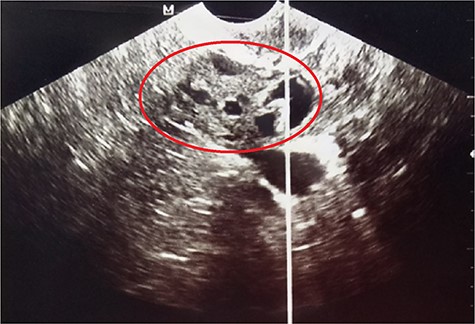

A 27-year-old nulligravida patient was referred to our hospital for an incidental ultrasonographic finding of a right-solid adnexal mass. She had no history of ovarian or thyroid disease. Physical examination revealed slight abdominal distension with no palpable pelvic mass or signs of ascites. The serum tumor marker, cancer antigen (CA)-125, was slightly increased at 4 IU/ml (reference value <35 IU/ml). Her pregnancy test was negative. Pelvic ultrasound revealed a right-solid cystic ovarian mass measuring 2.5 × 5.0 × 8.0 cm with intracystic vegetations (Fig. 1).

Pelvic ultrasound showing the right-solid cystic ovarian mass with intracystic vegetations (red circle).